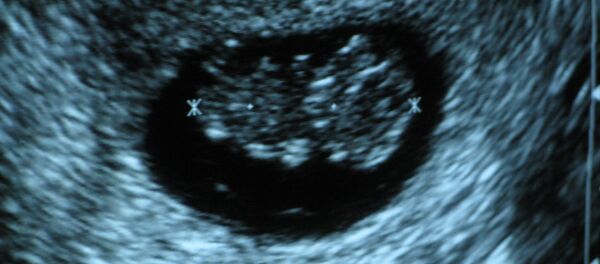

El secreto de su trabajo, como muestran los experimentos con embriones del pez cebra (Danio rerio), consiste en una proteína particular y el gen Meox 1, asociado con ella, que literalmente 'controlan' el crecimiento de órganos y definen qué células madre dejan de reproducirse una vez formado el embrión y se convierten en modelos de las células 'adultas', y cuáles conservan la capacidad de reproducirse y ayudar a los órganos a repararse en caso de lesiones o traumas.

El Meox1 y la proteína, según los investigadores, pueden controlar la formación de todos los órganos humanos y animales.